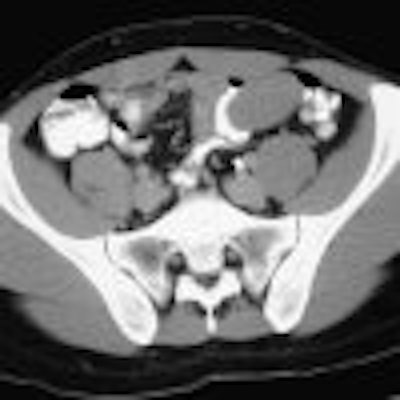

Chapter 7 -- The Pancreas

Located in the anterior pararenal space of the retroperitoneum, the pancreas occupies an anatomic location that is relatively accessible by clinical examination. The combined use of CT, MR, US, ERCP, and EUS has revolutionized pancreatic evaluation.

These complementary imaging modalities provide key information that guides clinical management for a diverse array of pancreatic diseases. Earlier diagnosis of pancreatitis and pancreatic ductal adenocarcinoma can lead to an improved clinical outcome.

In this chapter the clinical and imaging features of a variety of pancreatic diseases, including neoplasms, inflammatory conditions, and a host of other pancreatic conditions, are discussed.